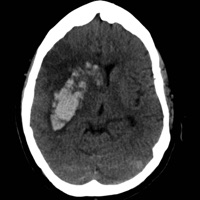

iPhone Screenshots

The HeRS (Hemorrhage Risk Stratification) calculator is an application that aids in determining the probability of hemorrhagic transformation of acute ischemic stroke in patients with an indication for anticoagulation. It is a prospectively validated score. The HeRS score is a prospectively validated equation based on continuous variables of age, renal function, and stroke size. The equation is complex and cannot be performed easily or quickly with paper or with an ordinary calculator. Determining the probability of hemorrhagic transformation of acute ischemic stroke is clinically useful as risk of hemorrhage often needs to be weighed against risk of recurrent stroke in deciding on whether or not to anticoagulate in the acute clinical setting. The HeRS score provides one of these valuable pieces of data- the likelihood of hemorrhagic transformation. Using the mobile application, the HeRS score can be accurately and easily determined rapidly.